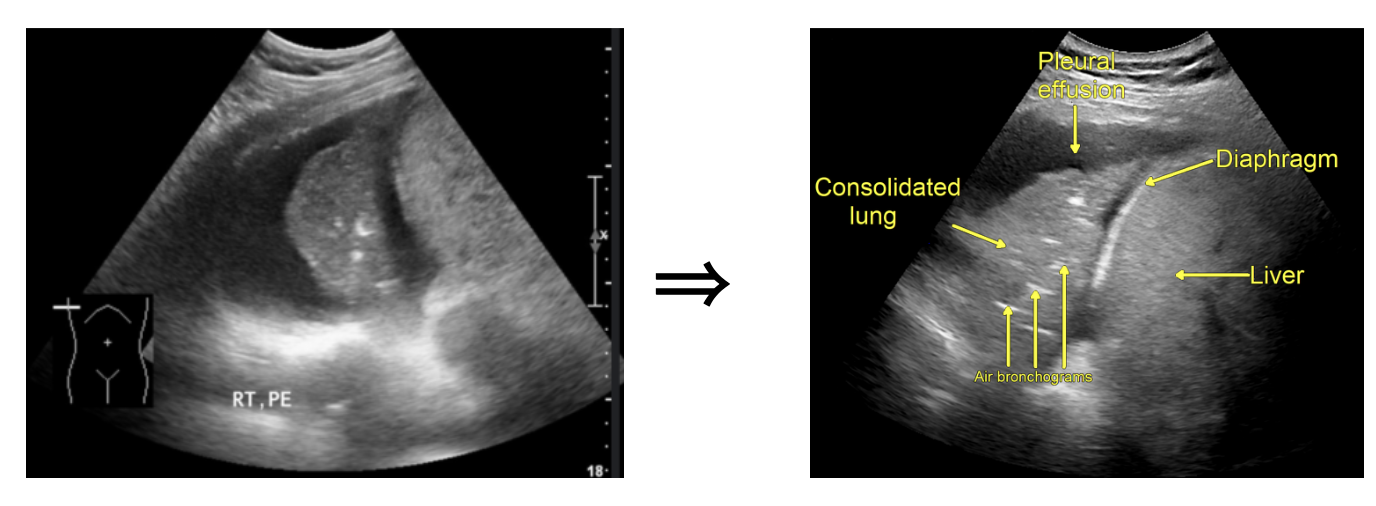

What do we see in this pt’s US?!

Right lung base

• Ultrasound is limited in air-rich organs bc air scatters ultrasound waves and cannot transduce them. Hence, typically cannot visualize normal lung tissue but... if there is consolidation and fluid...

• Fluid-filled alveoli act as an excellent acoustic medium and allow visualization of the lung parenchyma.

• air bronchogram occurs when endobronchial air is visible against a background of increased lung opacity.

Two Types

Static Air Bronchogram

• Immobile hyperechoic structure in consolidated or “hepatized” lung → indicating obstructed and trapped air → usually sign of atelectasis

Dynamic Air Bronchogram

• Mobile hyperechoic structure in consolidated or “hepatized” lung → indicating patent airway ⇒ pathognomonic for pneumonia

• Dynamic air bronchogram had a specificity of 94% and a positive predictive value of 97% for pneumonia.